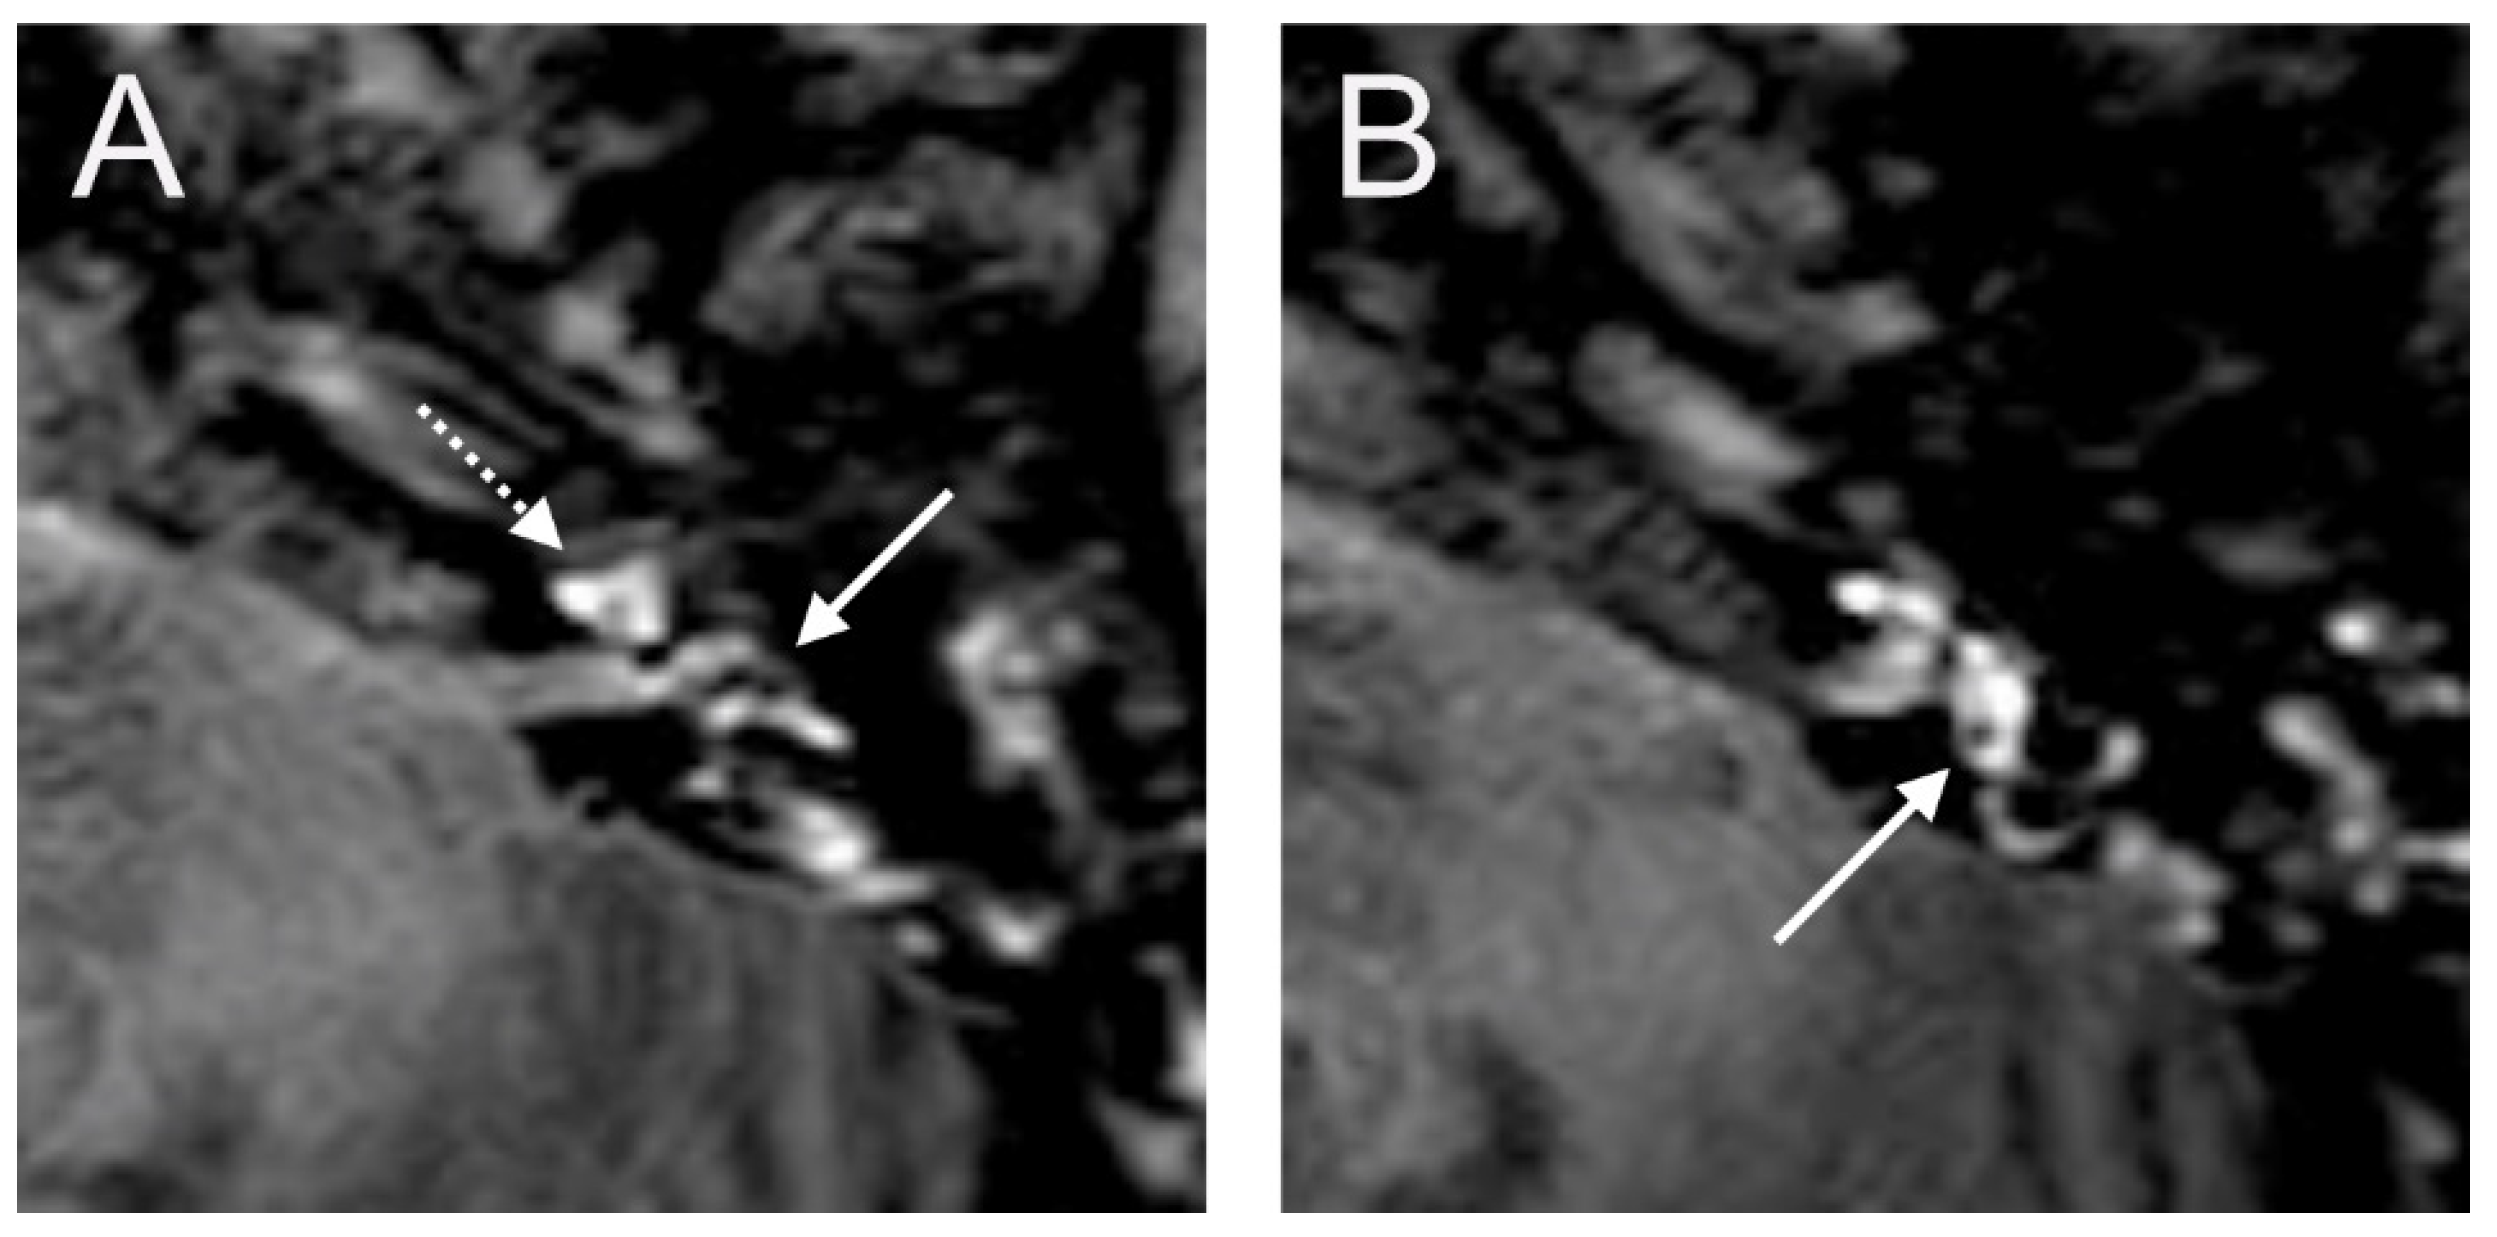

A 38-year-old female presented with a sudden hearing loss on the left side with acute rotatory vertigo without tinnitus. The visual examination showed a spontaneous nystagmus to the right side. The audiogram revealed a PTA of 110 dB on the left. Intraoperatively, a PLF track around the RW niche was observed, but the CTP on the left side was negative. Hyperintense signal intensity was found on T1- and CE-T1-weighted MRI sequences. On the T2 sequence, a hypointense signal in cochlear basal turn was found on the affected side in comparison to the contralateral side. In consideration of T1 and T2 sequences and acute symptom development, we assumed that labyrinthitis caused the sudden hearing loss in this case. On the 4 h delayed 3D-FLAIR image, a contrast enhancement was found in the cochlea, vestibulum, and fundus on the side of hearing loss (Figure 2).

Figure 2. A 38-year-old female presented with sudden hearing loss on the left side and acute rotatory vertigo. The axial 4 h delayed 3D FLAIR sequence shows a contrast enhancement in the left cochlea (A). A cochlear (arrow) and vestibular (dashed arrow) contrast enhancement was observed in the axial T1 sequence (B). Hypointense signal intensity in the basal turn of the left cochlea was found on axial T2W (C).